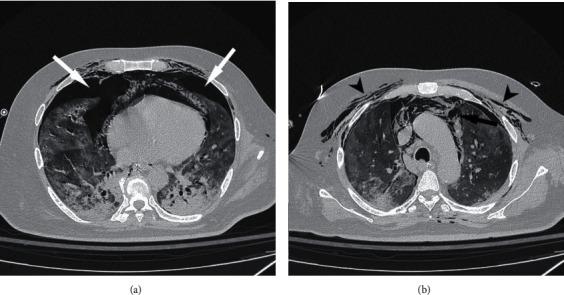

COVID-19 associated severe respiratory failure frequently requires admission to an intensive care unit, tracheal intubation, and mechanical ventilation. Among the risks of prolonged mechanical ventilation under these conditions, there is the development of tracheoesophageal fistula. We describe a case of a severe COVID-19 associated respiratory failure, who developed a tracheoesophageal fistula. We hypothesized that one of the mechanisms for tracheoesophageal fistula, along with other local and general risk factors, is the local infection due to the location of the virus itself in the tracheobronchial tree. The patient was managed successfully with surgical intervention. This case highlights the increased risk of this potentially life-threatening complication among the COVID-19 patient cohort and suggests a management strategy.

https://cdn.ncbi.nlm.nih.gov/pmc/blobs/2c85/8014238/94372e58ede1/CRIS2021-6645518.003.jpg

https://cdn.ncbi.nlm.nih.gov/pmc/blobs/2c85/8014238/4d346df252ca/CRIS2021-6645518.001.jpg

https://cdn.ncbi.nlm.nih.gov/pmc/blobs/2c85/8014238/9118d9ac8c0e/CRIS2021-6645518.002.jpg